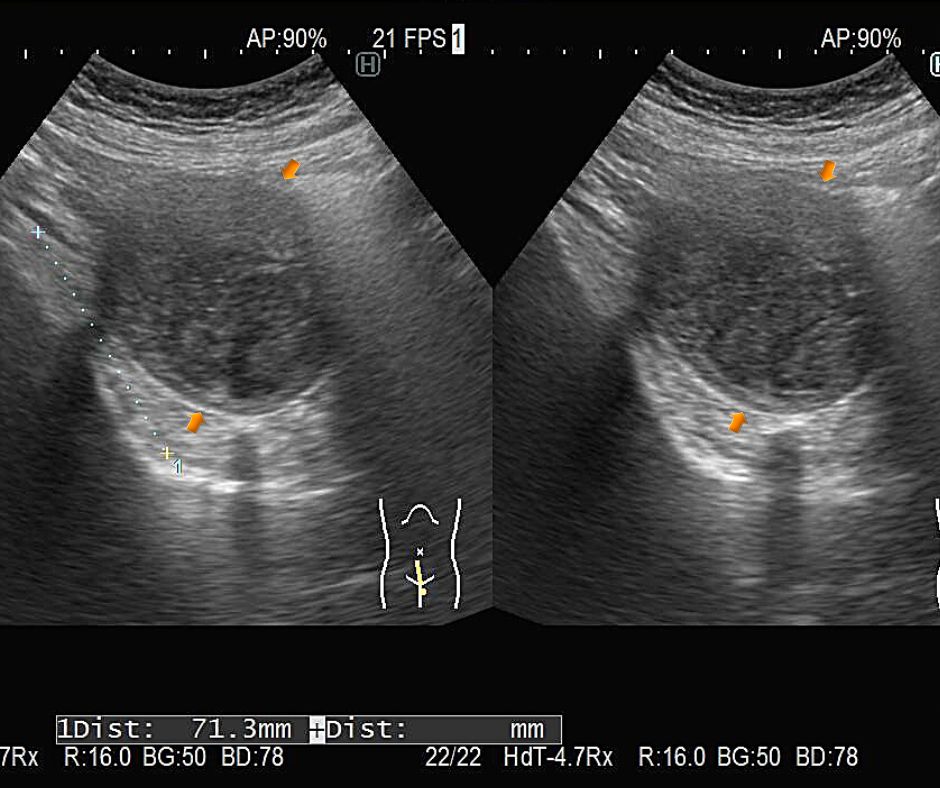

자궁근종의 진단은 일반적으로 초음파 검사를 통해 이루어집니다. 초음파는 비침습적인 안전한 방법으로, 자궁 근종의 수, 크기 및 위치를 확인할 수 있습니다. 경우에 따라, MRI나 CT 스캔을 통해 더 자세한 정보를 얻을 수 있습니다. 진단 후, 자궁근종 증상과 환자의 건강 상태를 고려하여 적절한 치료 방법을 결정합니다.